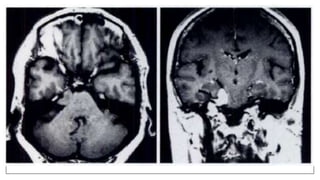

fMRI

• fMRI has contributed to improve our insight into how the human brain

works, both in the normal and diseased states.

• fMRI refers to the demonstration of brain function with neuro - anatomic

localization on a real time basis.

• The vast majority of these studies are performed using ‘Blood Oxygen

Level Dependent’ contrast or BOLD which requires the detection of very

small signal intensity changes

• They map the brain with fMRI to identify regions linked to critical functions

such as speaking, moving, sensing, or planning.

• Clinicians also use fMRI to anatomically map the brain and detect the

effects of tumors, stroke, head and brain injury, or diseases such

as Alzheimer's.